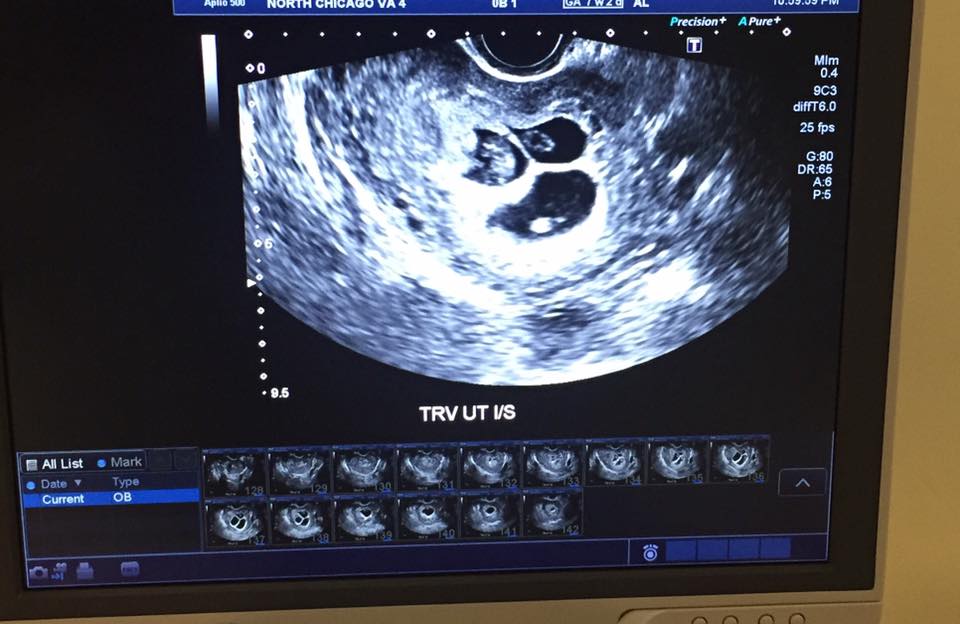

懷孕6週後的某一天,康特內一如往常地去做例行產檢,沒想到醫生卻告訴她一個天好的驚喜,讓她只想趕快分享給爸爸知道。

她興奮地在電話中告訴爸爸:「我的下巴驚掉了!醫生告訴我:『寶貝,妳懷了三胞胎。』」爸爸對於突然其來的好消息也相當激動,而康特內則表示:「我太開心了,我將再有3個笑臉,讓我不斷想起他(布萊恩)。」